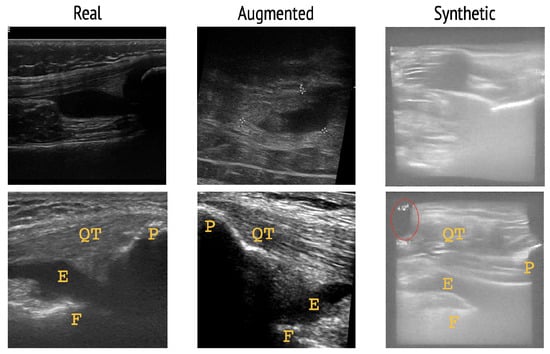

In Figure 6 and Figure 7, a visual comparison reveals that synthetic images are noticeably brighter than real and augmented images. This phenomenon was also observed in [11]. Additionally, real and augmented images exhibit more contrast, even after the brightness and contrast levels of synthetic images were adjusted. Anatomically, there are inconsistencies in the synthetic images, for example in the bottom row of Figure 1 within the red circled region, where the quadriceps tendon is abruptly cut off. Note, however, that the generation of anatomically correct synthetic images was not a primary objective of our work. Lastly, the geometric transformations applied to augmented images including horizontal and vertical flips, as well as rotation by up to ± 10 , makes them difficult to interpret, given the absence or repositioning of biological landmarks pertaining to the suprapatellar longitudinal view. The yellow annotations in Figure 6 and Figure 7 illustrate how flips and rotations affect the landmarks.

The near perfect correspondence between pixel intensity histograms for real and augmented images is due to many augmentations being geometric transformations. Unlike intensity or color transformations, geometric transformations do not affect the pixel intensity histogram of an image. Importantly, however, geometric transformations may reposition or conceal biological landmarks, meaning the augmented image becomes difficult to interpret and inconsistent with real images. This is particularly a concern for the CNN, which may then be encouraged to learn incorrect representations when trained on augmented images. In contrast, synthetic images portray more consistent anatomical structures than augmented images and contain resemblances to the three landmarks of the suprapatellar longitudinal view: The patella, femur, and quadriceps tendon. We emphasize, however, that the generation of anatomically accurate synthetic images was not a primary objective of our work and acknowledge that the synthetic images contain anatomical inaccuracies.

Figure 6. Real, augmented, and synthetic image samples of knee joint recess distension negative for thickened synovium. Labeled F: femur, P: patella, E: effusion, QT: quadriceps tendon. Red circle depicts region of anatomical inconsistency with incomplete QT.